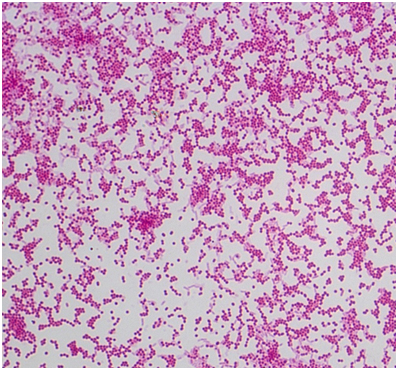

представників роду Staphylococcus з групи так званих «коагулозо-негативних» стафілококів, які раніше вважалися непатогенними. До них відносять S. xylosus, S. cohnii, S. simulans, S. capitis. Назва роду Staphylococcus пояснюється морфологією бактерій, які в пофарбованому за Грамом мазку схожі на виноградні грона (рис. 1).

S. aureus – грампозитивні, нерухомі бактерії, сферичної форми, діаметром 0,8-1,0 мкм, розташовані в мазках поодиноко або парами у вигляді скупчень, що нагадують виноградне гроно. S. aureus утворює пігмент золотистого кольору. Факультативні анаероби, культивуються при 35-40 °С і pH 7,0-7,5. Ферментують лактозу і маніт з утворенням кислоти, а в анаеробних умовах - глюкозу. При вирощуванні на середовищі з глюкозою утворюють ацетон. Відновлюють нітрити до нітратів або газоподібного азоту. Продукують коагулазу і некротоксин, культивуються на МПА і МПБ.

Рис. 1. Грам позитивні стафілококи, отримані із жовткового мішка, культивовані на середовищі МПА